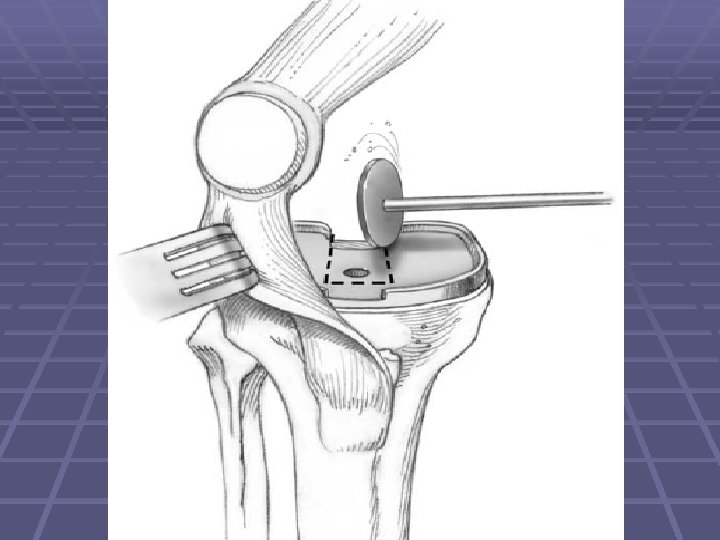

COMPONENT REMOVAL § The prosthesis-bone interface should be examined on both the tibial and femoral components § Remove the femoral component first because this allows better clearance for the tibial component

COMPONENT REMOVAL Cont. § The tibial component is removed in a similar fashion § The patellar component should be removed if there is evidence of patellar component wear